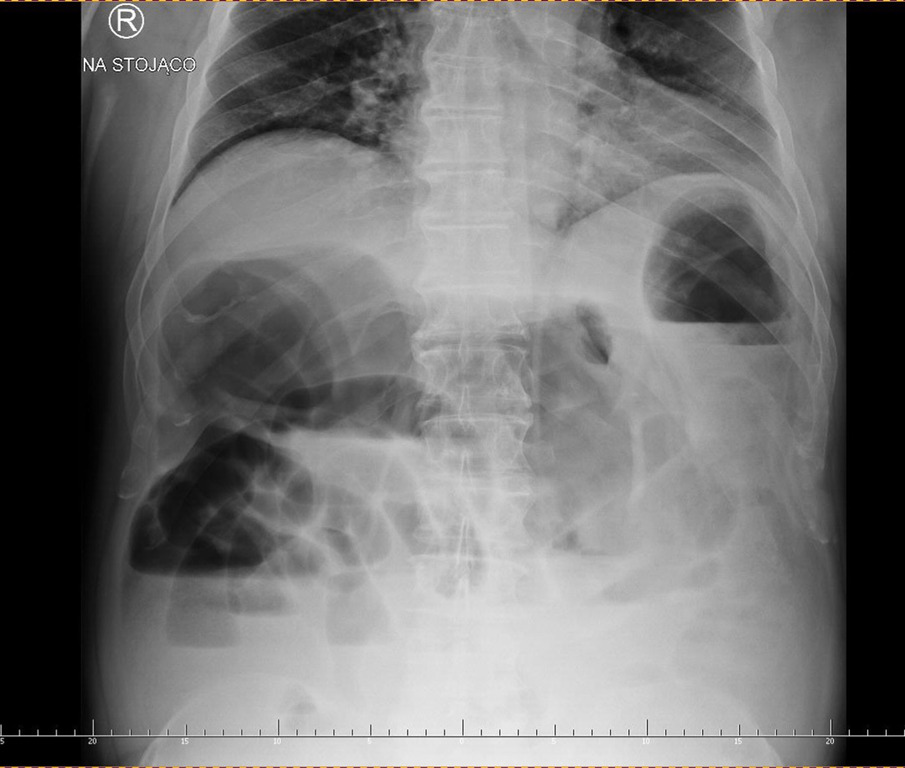

Diagnostyka: Wykonuje się przeglądowe zdjęcie RTG jamy brzusznej w celu potwierdzenia niedrożności (ryc. 1 i 2) i/lub tomografię komputerową (TK) ujawniającą rozdęte pętle jelit powyżej guza (ryc. 3).